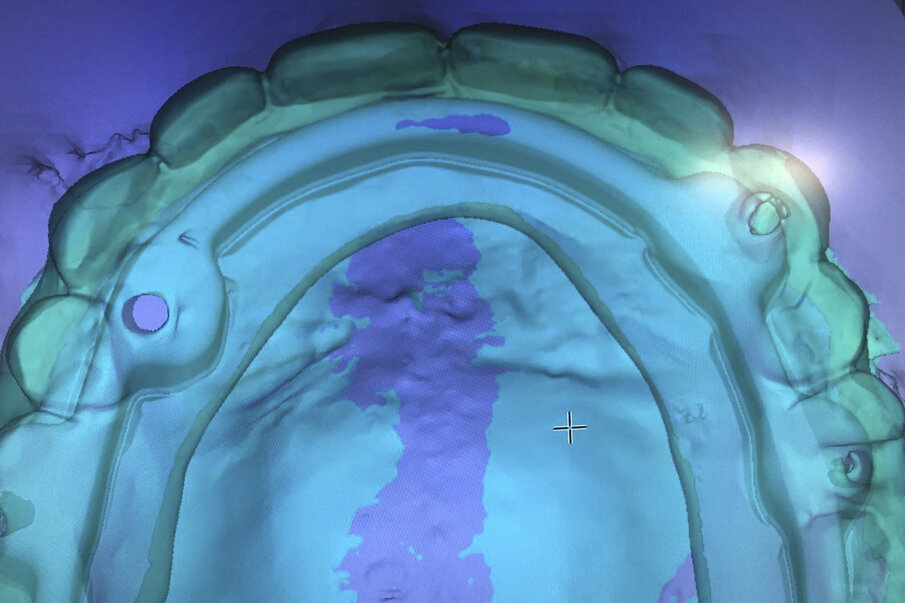

The dual-scan protocol was used to visualise bone, soft tissue thickness and denture position in the Simplant software (Dentsply Sirona). Four DS PrimeTaper EV 3.6 mm diameter implants were planned according to the position of the patient’s denture, and four Multibase abutments (Dentsply Sirona) were visualised accordingly (Fig. 3).

Prior to surgery, intra-oral scans of the edentulous upper jaw and dentate lower jaw were performed. The existing denture was used first as a surgical guide and then as a provisional prosthesis, after removing the palate (Fig. 4). Immediately after implant placement (Figs. 5–10), abutment position was registered with an intra-oral scan (Fig. 11). The provisional prosthesis was prepared fromthe existing denture (Figs. 12 & 13) and then the Atlantis BridgeBase was designed (Fig. 14).

Fig. 3: Implant treatment planning in Simplant using the dual-scan protocol to visualise tooth position as well as abutment position. Four DS PrimeTaper implants were planned for immediate restoration.